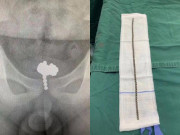

Cảnh sát đã tiến hành khám nghiệm tử thi và phát hiện bé Keziah mắc phải một hội chứng hiếm gặp có tên viêm đại tràng sigma. Căn bệnh này vô cùng hiếm xảy ra ở trẻ em và các bác sĩ trước đây từng chữa trị táo bón cho bé Keziah cũng không hề phát hiện ra.

Bác sĩ nhi khoa Andreas Marnerides cho biết, tình trạng này ảnh hưởng tới đại tràng, gây ra hàng loạt triệu chứng nguy hiểm như đau bụng, buồn nôn, sốt cao, táo bón, suy nhược cơ thể... Bác sĩ Andreas Marnerides đã tiến hành khám nghiệm tử thi và kết luận: "Khi đại tràng bị xoắn, nó có thể khiến máu không lưu thông được, dẫn đến hoại tử ruột và nạn nhân tử vong. Điều này rất khó được phát hiện. Nếu tôi là bố mẹ của nạn nhân, tôi cũng chỉ biết làm như họ".